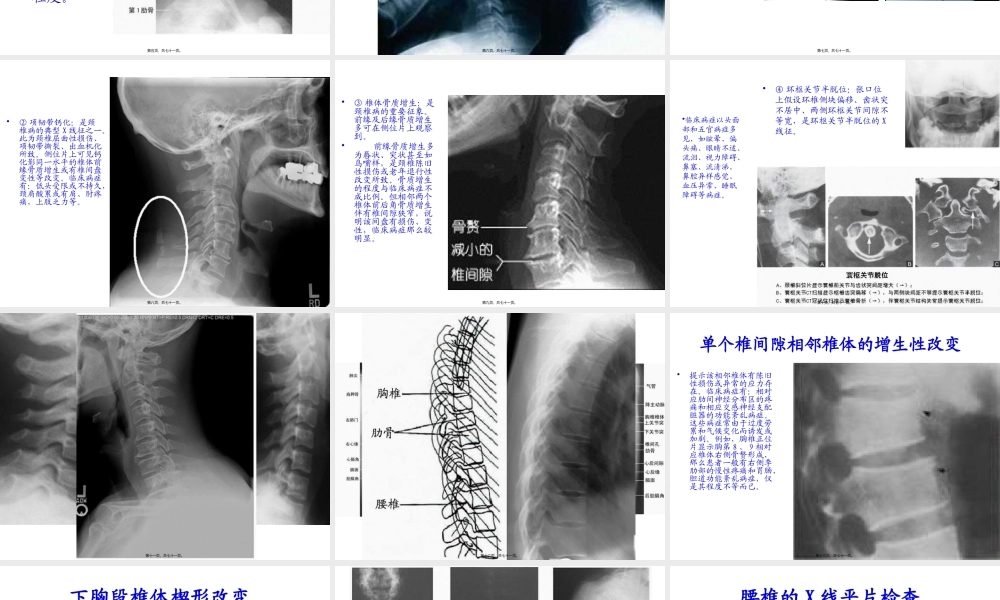

第一页,共七十一页。X线检查•X线检查是临床检查的一局部,对脊柱疾病有良好的诊断效果,许多脊柱疾病可以根据X线表现直接做出诊断,如骨骼畸形、外伤、肿瘤等,椎管内及脊柱附近的病变,亦可根据X线检查获得重要的诊断依据。另外,对治疗效果进行评价,X线检查也是重要的手段方法之一。〔X线技术为观察骨骼状态的主要方法〕第二页,共七十一页。颈椎的X线平片检查•①颈椎正位片:可观察棘突偏移、环枢关节半脱位、齿状突骨折或畸形、钩椎关节骨赘及横突肥大、颈肋、隐裂等。第三页,共七十一页。•②颈椎侧位片:可观察颈椎曲度、椎体前后缘骨赘、椎间隙改变、椎体滑脱、先天畸形、项韧带钙化、椎前软组织阴影的改变、椎管前后径、后关节错位等。第四页,共七十一页。•③颈椎左、右前斜位片:主要观察椎间孔有无狭窄及其狭窄的程度。第五页,共七十一页。•④功能位片:即过屈、过伸、左右倾斜位等。可动态观察椎体滑移、棘间韧带损伤等常规位X线片无法显示的X线征。第六页,共七十一页。常见的颈椎异常X线征•①生理曲度改变:颈椎生理曲度消失或反张,多见于颈椎软组织急性损伤、颈椎间盘突出或变性以及有神经根刺激病症者。临床上除具有其各自病损所致的病症外,尚有咽部异物感、吞咽障碍、恶心以及颈肩沉重、酸痛等病症。第七页,共七十一页。•②项韧带钙化:是颈椎病的典型X线征之一。此为颈椎屈曲性损伤、项韧带撕裂、出血机化所致。侧位片上可见钙化影同一水平的椎体前缘骨质增生或有椎间盘变性等改变。临床病症有:低头受限或不持久,颈肩酸累或有肩、肘疼痛,上肢乏力等。第八页,共七十一页。•③椎体骨质增生:是颈椎病的重要征象。前缘及后缘骨质增生多可在侧位片上观察到。•前缘骨质增生多为唇状、突状甚至如鸟嘴样,是颈椎陈旧性损伤或老年退行性改变所致。骨质增生的程度与临床病症不成比例。但相邻两个椎体前后角骨质增生伴有椎间隙狭窄,说明该间盘有损伤、变性,临床病症那么较明显。第九页,共七十一页。•④环枢关节半脱位:张口位上假设环椎侧块偏移、齿状突不居中、两侧环枢关节间隙不等宽,是环枢关节半脱位的X线征。•临床病症以头面部和五官病症多见,如眩晕、偏头痛、眼睛不适、流泪、视力障碍、鼻塞、流清涕、鼻腔异样感觉、血压异常、睡眠障碍等病症。第十页,共七十一页。•⑤钩椎关节骨质增生性改变:正位片上如显示单个椎间隙钩椎关节骨质增生,说明该相邻椎体有陈旧性损伤或椎间盘变性,病损一侧或两侧钩突...

3、如文档内容存在违规,或者侵犯商业秘密、侵犯著作权等,请点击“违规举报”。

碎片内容